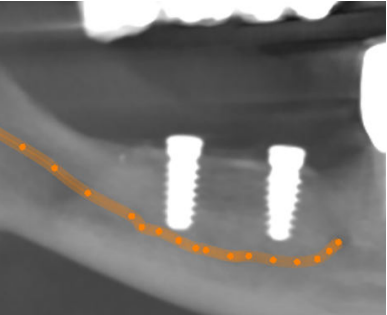

Se presenta el caso de un paciente varón de 73 años, que en octubre de 2017 acudió a la consulta refiriendo una hipoestesia del hemilabio inferior derecho, precedida de una anestesia hemilabial, asociada a la colocación de implantes osteointegrados en el cuarto cuadrante dos años atrás. Su estado de salud general es bueno y no es fumador. Durante la exploración intraoral se observó movilidad de grado II en el diente 45 y la exposición de las espiras de los implantes correspondientes a los dientes 46 y 47, además de supuración a la palpación de la zona. En la exploración radiológica, mediante radiografía panorámica, se evidenció una gran pérdida ósea alrededor de ambos implantes que también afectaba al diente 45 y se observó la invasión del conducto del nervio dentario inferior por el ápice de los implantes. Asimismo, se realizó una tomografía computarizada de haz cónico (CBCT), que confirmó la presencia de los ápices de ambos implantes en el conducto nervioso (Figura 1).